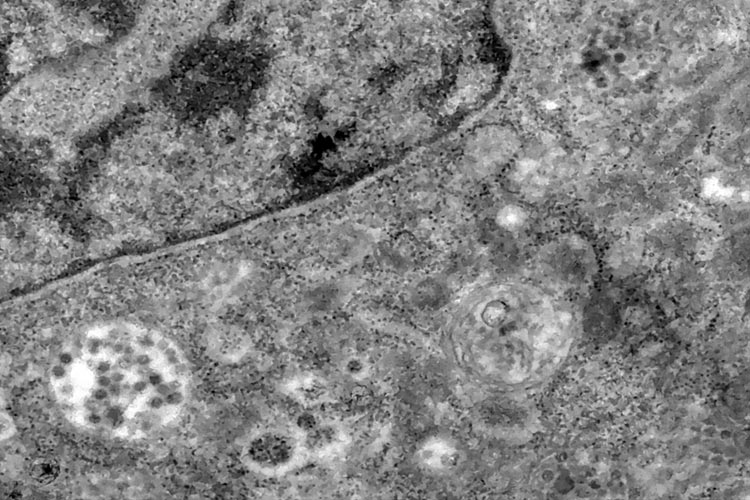

Medidas de distanciamento podem ser necessárias até 2022, diz estudo Foto: IOC/Fiocruz

Estudo publicado na revista “Science” nesta terça-feira (14) por cinco cientistas da Universidade Harvard (Estados Unidos) mostra que medidas de isolamento social para conter a pandemia do novo coronavírus podem ser necessárias até 2022 — caso não haja vacina ou tratamento capazes de conter a Covid-19. O artigo ressalta que um distanciamento social adotado de forma intermitente enquanto o coronavírus circular “poderia prevenir que a capacidade das UTIs sejam excedidas”. Com a capacidade atual, a pandemia de Covid-19 pode durar até 2022 desde que essas medidas de afastamento sejam adotadas para evitar uma sobrecarga no sistema de saúde. Assim, os cientistas de Harvard afirmam que há duas possibilidades para reduzir a duração da pandemia e das medidas de distanciamento social: Aumentar a capacidade do sistema de saúde; Introduzir um tratamento que corte pela metade a proporção de infectados que necessitem internação.